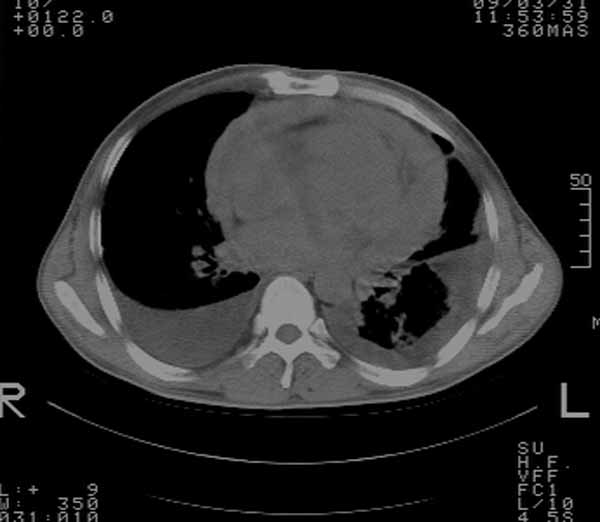

以下是引用余辉在2009-3-31 18:43:00的发言:[br]肺水肿,双侧心腔积液,心包积液,心影增大,疑似心衰

以下是引用wangyong1977在2009-3-31 20:46:00的发言:[br]肺水肿,双侧胸腔积液,心包积液,心影增大,疑似心衰 [br]

以下是引用宇宙ct在2009-3-31 18:57:00的发言:[br]肺水肿,双侧心腔积液,心包积液,心影增大,疑似心衰 [br] [br]